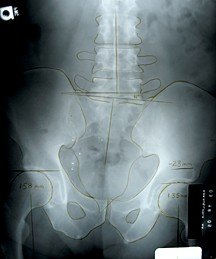

It seems universally accepted that the only accurate measurement for LLI is an erect A-P pelvic X-ray with center beam through the top of the femur heads. Great care should be taken in proper patient placement and posture. Once in position, I instruct a patient to fully extend both knees, bring them forward equally to a point of comfort, and then hold. One also should be aware of the effect unilateral hyperpronation of the ankle and foot may have on leg-length measurement. To compensate for such a development, I instruct the patient to roll both feet outward and then slowly lower them until both feet are properly balanced with a vertical Achilles' tendon. The X-ray tube should be absolutely perpendicular to the film with the center of the beam at the ilio-femoral joint space, hitting the middle of the film.

Once a good image has been secured, measuring from the bottom of the film to a horizontal line drawn at the top of the femur heads will give a comparative difference indicating true leg-length inequality.

One also may measure a line at the sacral base against horizontal for the angle of sacral base declination. For those wishing to identify which of the lower extremity long bones is short or in what combination, one may use the same technique to get an A-P bilateral knee view. I have even done this combined, using collimation for a split-screen view on 14"x17" film mounted vertically.